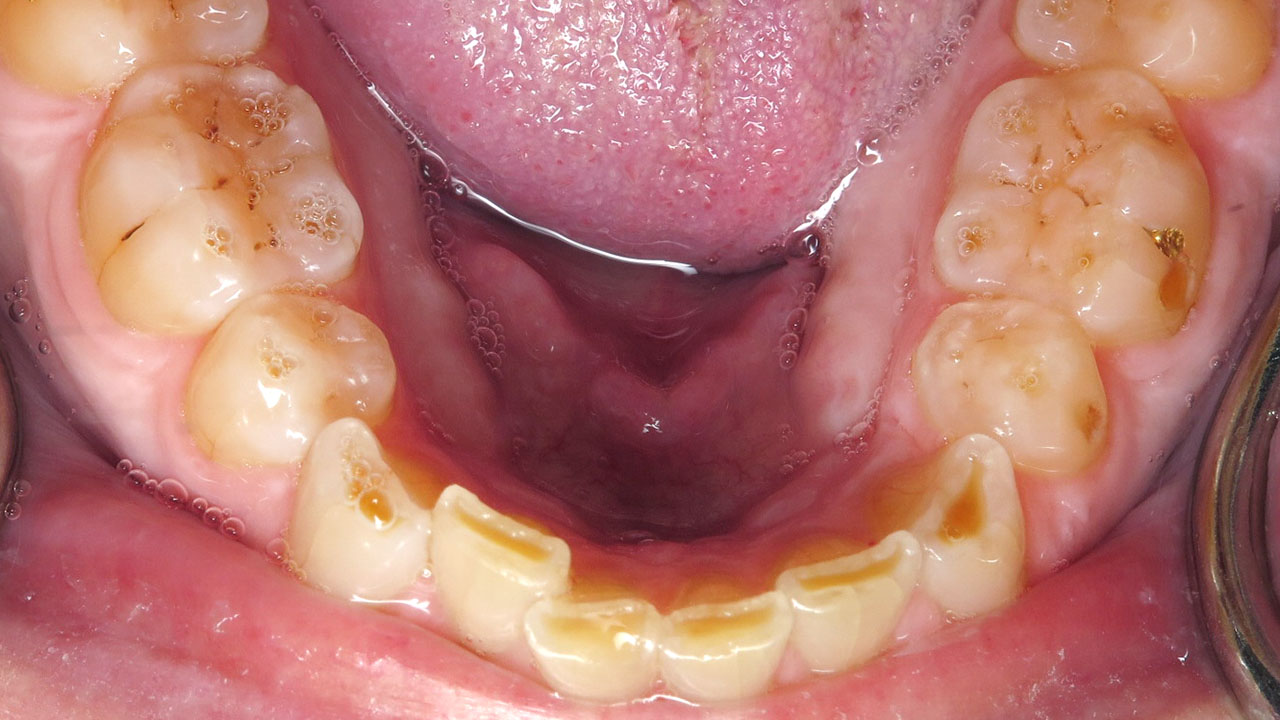

The patient noticed that her front teeth had become sharp and were catching her tongue and lip. She had also noticed darker areas developing near the edges of her upper front teeth. She was aware that she grinds her teeth and already wore a nightguard.

This patient came to the office because her front teeth had begun to feel sharp and were catching her tongue and lip during normal function. She had also noticed darker areas forming near the edges of her upper front teeth.

The patient was aware that she grinds her teeth and had been wearing a nightguard. Over time, the grinding had worn through the protective enamel on the edges of several teeth, exposing the underlying dentin. In some areas, early decay had begun to develop within the exposed dentin.